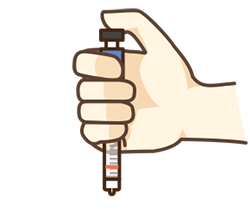

妊娠期糖尿病(GDM)和2型糖尿病孕妇需要控制血糖,除了注意饮食方面外,运动对于控糖是必不可少的。 孕期适量运动非常重要,“糖妈妈”在孕期适度运动可以控制体重,还能增加胰岛素的敏感性,对维持血糖稳定,减少胰岛素用量都很有作用。国内外多部指南均鼓励“糖妈妈”进行合理的体育运动。对于准妈妈而言,运动可以增加肌肉力量,促进肠蠕动,减少便秘,还能降低巨大儿的发生率,促进正常分娩。 温 馨 提 示 在整个孕期都可以运动,“糖妈妈”在孕期坚持适度运动对自身和宝宝均有益处,只要没有运动禁忌,就“动”起来吧! #孕期居家,控糖保卫战# 疫情反复,居家的日子里,孕妈控糖很关键。均衡营养以外,科学运动,为宝宝创造健康的成长“环境”很重要。 【专业视频指导 健康安心孕育】居家孕妈,开启控糖保卫战! 快来跟着视频一起学习吧~ “糖妈妈”在孕期适合做哪些运动? 有氧运动可作为糖妈妈主要的运动方式,包括散步、游泳、固定自行车、慢跑、孕期瑜伽、太极拳等。大家还可以进行一些低负荷的抗阻训练,如利用弹性阻力带进行练习。具体的运动量还需要根据个体在孕前的活动情况、自身的健康问题而定。关于运动的具体方式、频次、时间以及强度可听取医生的专业建议。 孕期推荐的运动方式是散步,每天的运动时间可维持30-60分钟。另外,随着孕周的增加,运动量需要逐渐减少,运动方式和强度也要根据自身情况进行调整。 温 馨 提 示 “糖妈妈”运动前要听取医生建议,并根据自身情况随时进行调整。步行运动最常用也最适宜,可每日坚持。 “糖妈妈”运动的注意事项 “糖妈妈”开始运动前,需要到产科医生处进行检查和咨询,由医生评估自身情况,判断是否适宜进行运动。 运动时要着宽松的衣服、合适的胸罩和平底防滑的鞋子。避免在炎热、潮湿的环境中运动。运动前后还需要测血糖,当血糖<3.9mmol/L或>13.9mmol/L时,应暂停运动。 运动时要注意防止低血糖反应和延迟性低血糖,可随身携带饼干或糖果,在有低血糖征兆时及时服用。 常见的低血糖表现有饥饿感、乏力、震颤或颤抖、出汗多、易激动、失去知觉、意识模糊等。运动结束后可进行一些拉伸和放松训练。 对于应用胰岛素治疗的“糖妈妈”在运动时还需要注意: 1 避免在清晨空腹未注射胰岛素之前进行运动,同时也要避开胰岛素作用的高峰期。 2 胰岛素注射部位要避开进行运动的肢体,防止肢体运动引起胰岛素吸收加快而引发低血糖反应。 3 运动前要先测量血糖值,如果空腹血糖<5.5mmol/L,运动前应适当补充饮食。 温 馨 提 示 “糖妈妈”在孕期运动要以安全为主,注意防止低血糖,科学合理的运动可以让怀孕过程更加顺利。 责任编辑:苏石 责任排版:小胖 图片来源:摄图网、糖护士